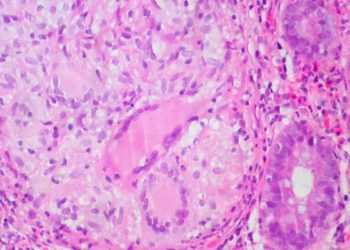

Strictures occur in an estimated 15-30% of Crohn’s Disease (CD) patients within the first 10 years after diagnosis. Several methods have been developed for evaluating small-bowel strictures, including computed tomography enterography (CTE) and double-balloon enteroscopy (DBE). CTE is very effective at detecting small-bowel disease, with a sensitivity and specificity of 83% and 88% respectively. Meanwhile, DBE has the benefit of allowing direct visualization while obtaining biopsies for histopathologic analysis. However, the relationship between symptom severity and the strictures detected through DBE is unknown. Therefore, this prospective cohort study aimed to determine the detection rate of DBE for CD patients with small-bowel symptomatic strictures. The study participants were enrolled from a single centre in China. All received both CTE and DBE, within one month of each other. The symptom severity was assessed through the Crohn’s Disease Obstructive Score (CDOS), with patients divided into low severity (scores 1-3) and high severity (scores 4-6). In total, there were 165 CD patients included, 42.4% of whom had low severity symptoms. The study found that detection rates of 92.7% and 85.5% through DBE and CTE respectively. For DBE, the rates were 91.4% and 94.7% in the low severity and high severity groups respectively (p = 0.13), whereas for CTE, the detection rate was greater in the high severity than the low severity group (90.1% and 75.9% respectively, p = 0.01). Overall, this study demonstrated that DBE is a very effective method for diagnosing small-bowel strictures in CD patients, with no difference depending on symptom severity.